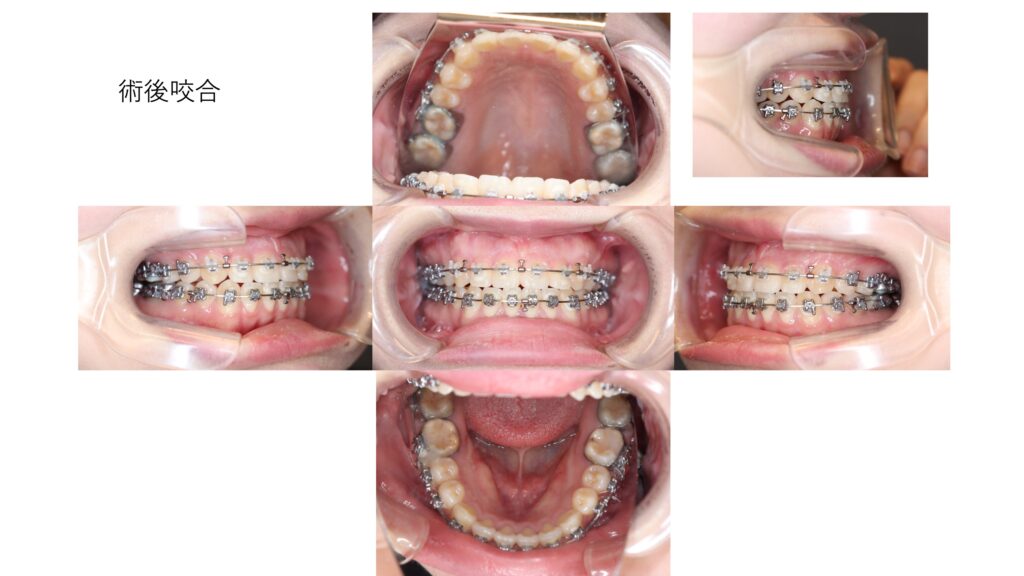

術後は前歯のすき間がなくなり、しっかりとかみ合う状態になりました。

口元の突出感もやわらぎ、さらにあご先(オトガイ)を前に出すことで、横顔のバランスも大きく改善しています。

機能面だけでなく、見た目の印象も自然で調和のとれた仕上がりになりました。